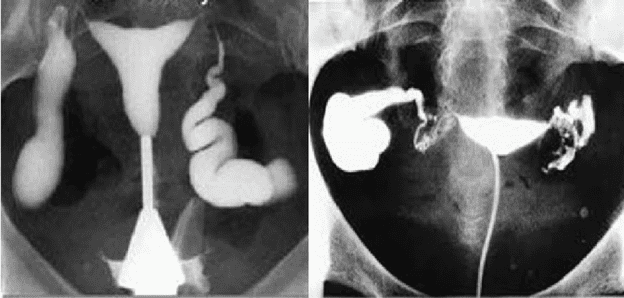

Chụp X-quang tử cung vòi trứng là một kỹ thuật hình ảnh y tế được sử dụng để xem xét tử cung, vòi trứng và các cơ quan xung quanh bằng cách sử dụng tia X và máy ảnh đặc biệt. Kỹ thuật này cho phép các chuyên gia y tế xem xét các vấn đề liên quan đến sức khỏe phụ nữ, bao gồm các vấn đề về sản xuất và sinh sản.

Mục đích của chụp X-quang tử cung vòi trứng là để xác định các vấn đề liên quan đến sức khỏe phụ nữ, bao gồm các vấn đề về sản xuất và sinh sản. Kỹ thuật này có thể được sử dụng để xác định các vấn đề như:

- Một chất tạo contrast sẽ được tiêm vào cổ tử cung để giúp các cơ quan trông rõ hơn trên hình ảnh.

- Máy ảnh sẽ được đặt gần khu vực cần xem xét và các tia X sẽ được phát ra.